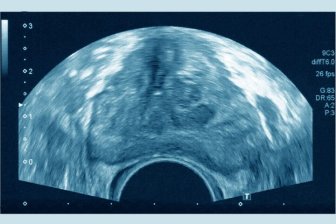

Higher risk of aggressive prostate cancer in Indigenous men, study showsThe study, published Monday in the journal Cancer, looked at prostate cancer screening data among almost 1.5 million men in Alberta between 2014 and 2022.HealthJul 10, 2023